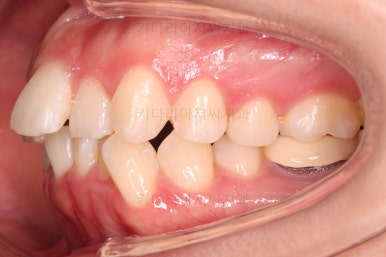

초진 시 입안의 모습입니다.

전반적으로 치열이 삐뚤고, 특정 앞니는 톡 튀어나가 미적으로 좋지 못한 상황이었습니다.

이갈이, 이악물기 습관도 있어서 앞니는 삐뚤어진 채로 치아가 많이 갈려있는 상황이었습니다.